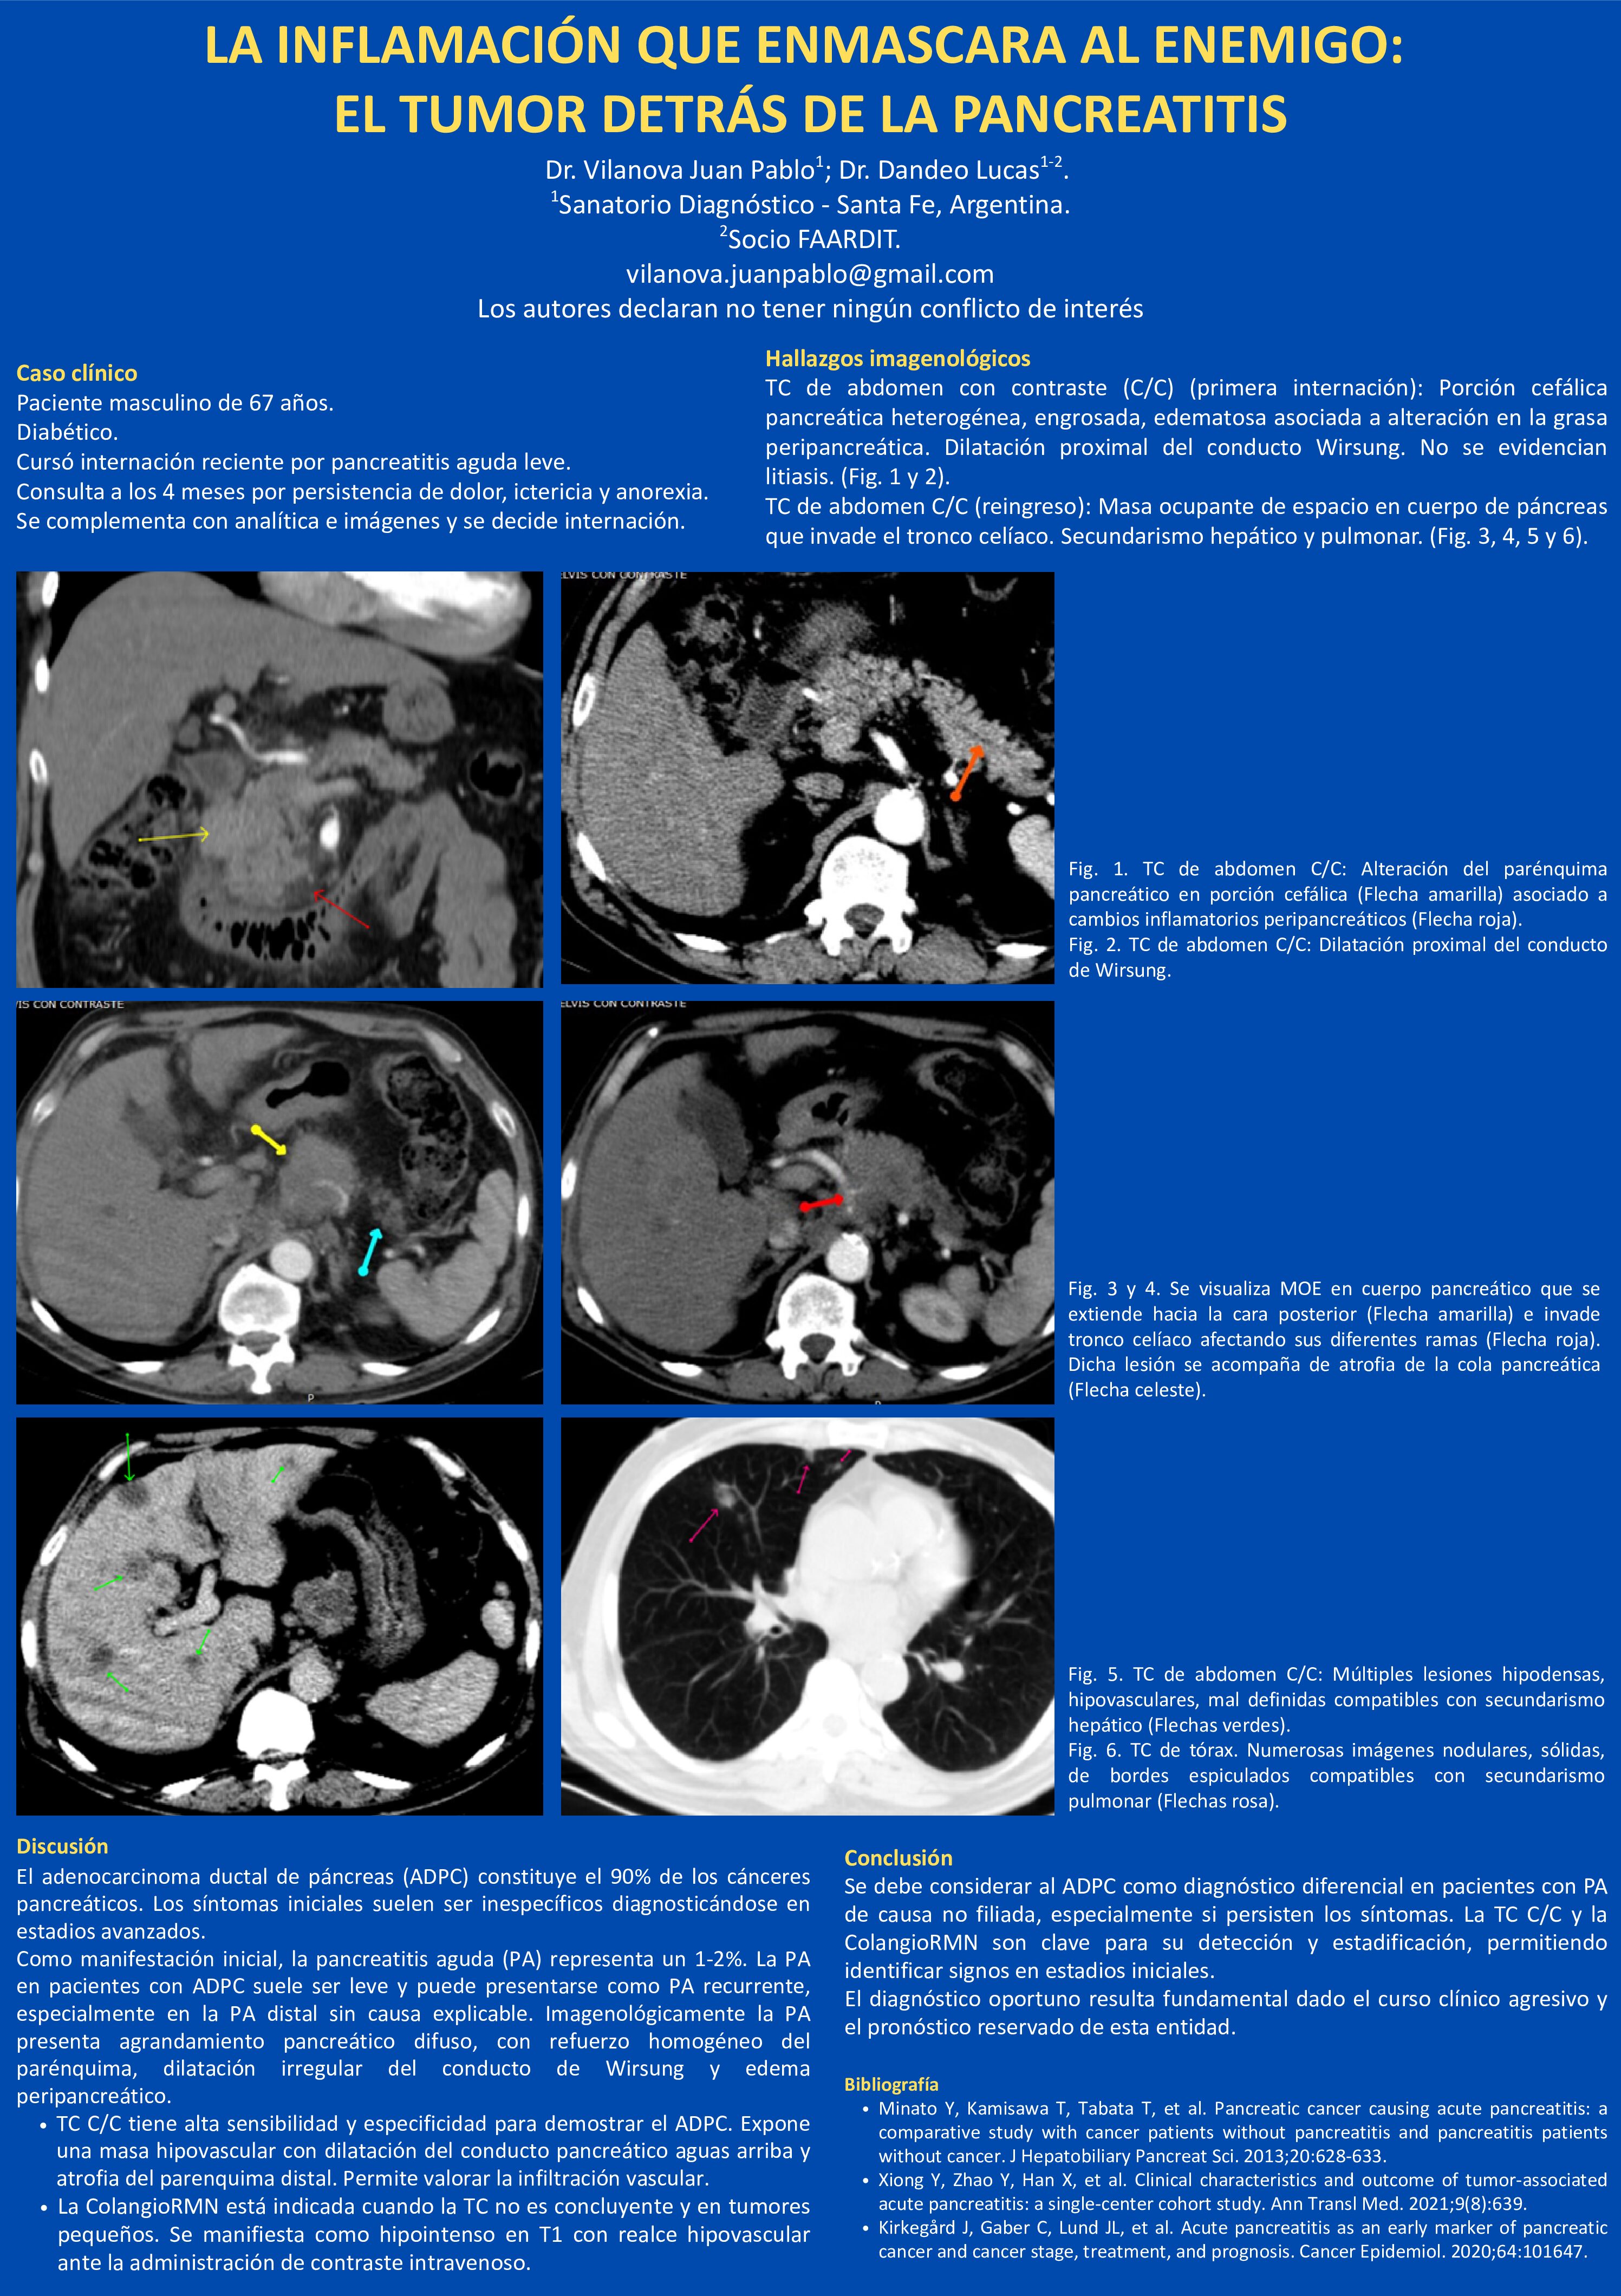

LA INFLAMACIÓN QUE ENMASCARA AL ENEMIGO: EL TUMOR DETRÁS DE LA PANCREATITIS

10/07/2025